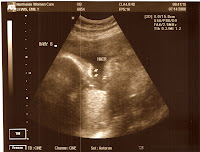

We had a doctors visit on Monday, July 14th. It was an uneventful appointment besides the fact that we received ultrasound photos (see below). We also learned that the babies have gained nearly 1 lb. since our last doctors visit. They now way 2 lbs. 9 ounces & 2 lbs. 11 ounces. They weighed in well and all of their measurements were in an acceptable range.